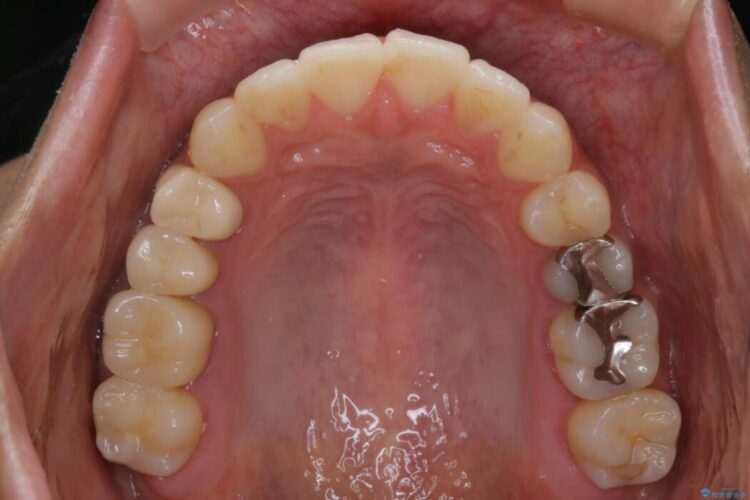

歯列のガタガタと飛び出ている前歯を治したいとのことで来院されました。

装置の範囲内で可能な限り前歯の位置を動かし整えるため、マイクロインプラントを用いて遠心移動をする歯列矯正を計画しました。

本症例では上顎前突(出っ歯)や歯列のがたつきを改善するスペースを確保するために、歯を遠心移動をサポートすることができるマイクロインプラントを用いたゴムかけを行っていただきました。

それにより従来の矯正治療と比べましても効率的に歯の移動を行えるため、非抜歯の場合でも歯列を整えることが可能となります。